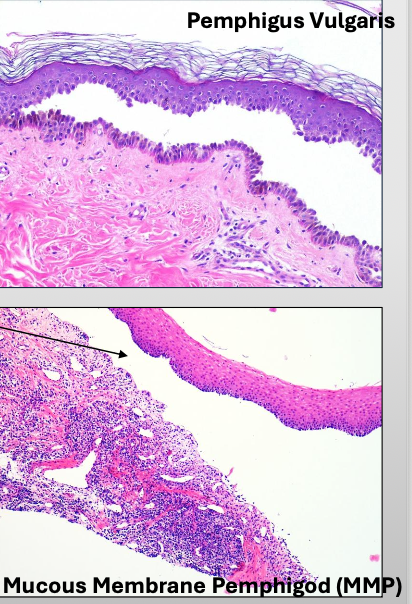

What is Vesiculo-bullous Disease look like histologically?

What is acantholysis in Pemphigus Vulgaris?

Epithelial cell separation “INTRA-EPITHELIAL”

Biopsy and Direct immunofluorescence (DIF)- INTRA-EPITHELIAL separation

What is Mucous Membrane Pemphigoid?

With scarring (cicatricial pemphigoid)